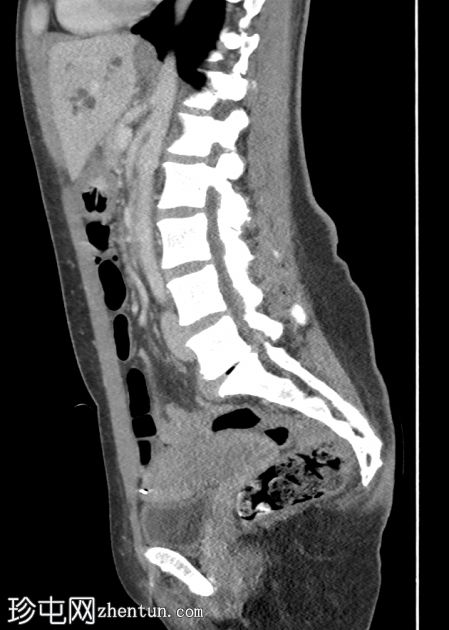

矢状位增强扫描(门静脉期)

肝内和肝外胆管中度扩张,胆总管(13 mm)内可见一小块边缘不透光结石(8 mm)。

胆囊壁轻度增厚,可能继发于慢性胆囊炎。未见管腔内结石。

双侧输卵管结扎术。

右侧股骨动力髋螺钉。